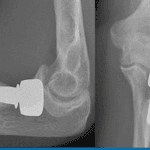

X-rays

are typically ordered to evaluate the underlying bone. They commonly reveal a bone lesion altering the bone’s shape and strength, often appearing enlarged with a clear central space and thin cortex.

MRI scans may be ordered following X-ray review, with CT scans reserved for rare cases.

The surgical technique of wide resection, or en bloc resection, involves excising a significant portion of bone containing the cyst. Typically, this approach is reserved for severe bone damage or recurrent cysts.

Wide resection often necessitates bone reconstruction using donor bone (allograft) or artificial implants, such as metal bone replacements.